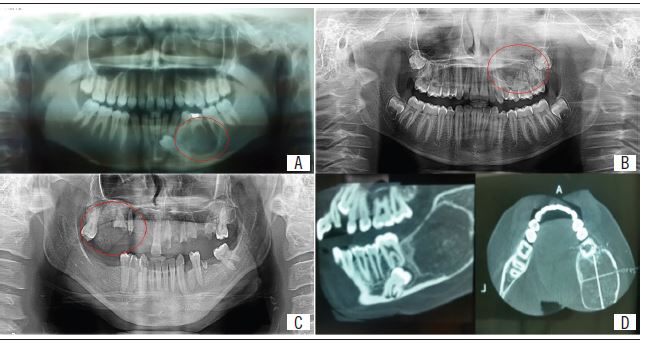

Regarding the radiographic aspect, the most common pattern was well-defined radiolucency, which showed radiopaque foci (Figure 1). Painful symptomatology was reported in three cases. Regarding treatment and relapses, more conservative surgical treatment presented higher recurrence rate, as shown in cases 4 and 6 (Table 1).

Radiographically, a well-defined lesion with areas of radiolucency and/or radiopacity is evidenced. The variation of these degrees is observed by the amount of mineralized tissue deposited in the lesion(16-18). In addition, root displacement and resorption may occur(19). In the reported cases, the well-defined radiolucent pattern with radiopaque foci was the most frequently observed pattern; areas of root resorption or divergence were not found.